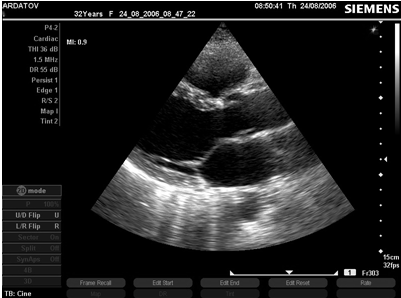

Рис. 7. ПМК, М- и В-режим, длинная ось левого желудочка, парастернальный доступ.

Двухмерная ЭхоКГ

1.       Выгибание одной или обоих створок за линию коаптации (проекцию митрального отверстия) в парастернальной проекции длинной оси левого желудочка или апикальной проекции.

2.       Утолщенность и избыточность створок.